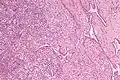

Vertical section of the testis, to show the arrangement of the ducts. Micrograph of the rete testis involved by seminoma. H&E stain.

Micrograph of the rete testis involved by seminoma. H&E stain. Tubular ectasia of the rete testis